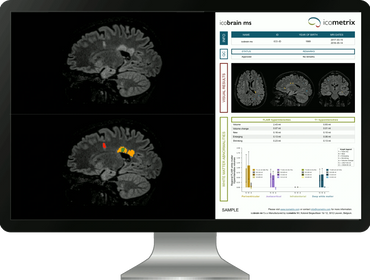

In the AssistMS trial, neuroradiologists and radiologists will assess MRI scans both with and without the support of icobrain ms, an AI tool designed to detect subtle changes in the brain.

The software being tested in the AssistMS trial, called icobrain ms, analyses brain MRI scans to detect and highlight small changes over time. It also creat

The software being tested in the AssistMS trial, called icobrain ms, analyses brain MRI scans to detect and highlight small changes over time. It also creates easy-to-read summary reports. The goal is to help doctors make better decisions about disease-modifying treatments (DMTs). By spotting signs of disease activity earlier and more accurately, clinicians can decide more quickly if a treatment change is needed.

In clinical practice, regular magnetic resonance imaging (MRI) is the only established tool for DMT efficacy monitoring. However, detecting the often subtle changes by inspecting MRI scans is time consuming, tiring and therefore error-prone. icobrain ms is a validated AI technology enabling quantification of MRI datasets, summarising findings in a structured electronic report as well as annotated images highlighting areas of change that help guide assessment. icobrain ms complements visual assessment of MRI scans and helps the clinician to decide whether or not a change in DMT is warranted.

icobrain ms—a validated AI-powered technology—complements traditional visual MRI analysis by automating lesion detection and quantifying disease activity with precision. By streamlining this process, it empowers clinicians to make timely, data-driven decisions about modifying Disease-Modifying Therapies (DMTs).